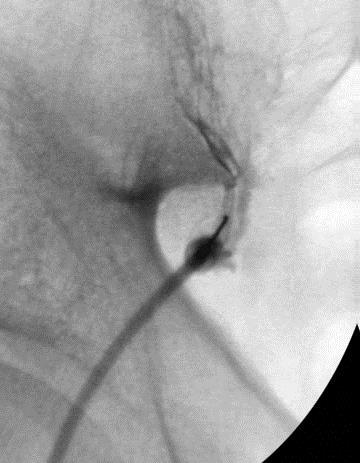

Sacroiliac joint injections with local anaesthetic and steroids have the strongest evidence supporting their use, but injection done without imaging control has been shown to be inconsistent. It is a requirement for effective injection to use fluoroscopy (X-ray imaging) or CT scans to confirm correct intraarticular positioning. A/Prof Woodgate also prefers to have arthrogram images to confirm localisation, which is best seen on CT images. The arthrogram will also demonstrate areas of capsular or ligamentous deficiency.

Prolotherapy involves a programme of injections (usually 3 injections done 3-4 weeks apart) of a glucose-based solution (typically 50% Dextrose) into the sacroiliac joint. To perform this injection properly usually requires CT scan control, combined with an arthrogram (the injection of dye into the joint) to confirm correct positioning. The injection creates an inflammatory response that results in fibroblast migration and increased ligamentous and capsular scarring. It is postulated that this extra capsular and ligament scarring result in less movement or hypermobility of the joint, which then causes less irritation to the rich nervous plexus surrounding the joint, and therefore less pain.